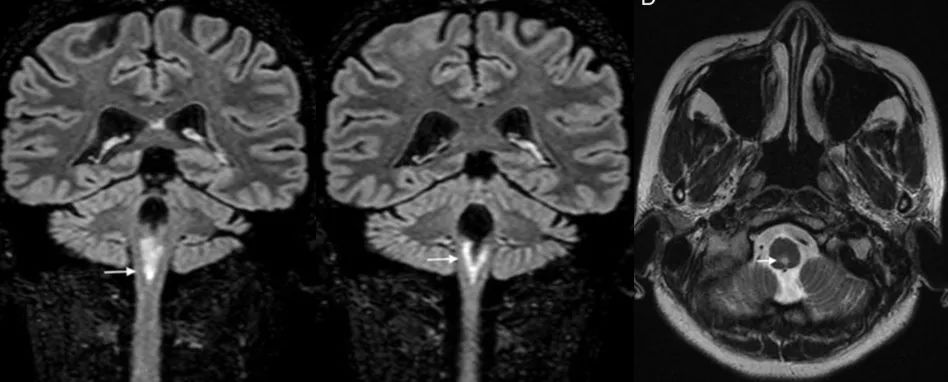

患者,女,45岁。主要症状为持续打嗝、呕吐、吞咽困难、眩晕,多动,上视性眼球震颤。患者完善脑脊液检查,提示AQP4(+)

答案:AQP4(+)的视神经脊髓炎,极后区综合征

极后区又称最后区,位于第四脑室底后部水平、孤束核和延髓的背侧面。极后区主要由缺乏紧密连接的有孔毛细血管供血,且缺乏正常的血脑屏障,对许多不能进入其他脑组织的蛋白质、多肽具有通透性。此区的星形胶质细胞富含水通道蛋白4(AQP4)抗原,因此容易成为AQP4抗体损伤的部位。极后区综合征(APS)是指无法用其他原因解释的顽固性呃逆和/或恶心、呕吐。

如果患者表现为急性或亚急性起病的恶心、呕吐和呃逆(单独出现或合并其他症状),发作性或持续性,症状存在≥48h(如MRI可见极后区新发病灶,则症状存在时间短(<24h)时也需考虑);对症治疗(静脉补液,止吐药物,呃逆治疗)并不能完全好转,排除其他病因后就要考虑NMOSD极后区综合征。